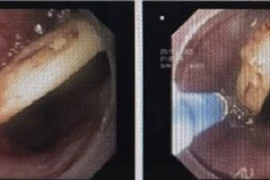

Các bác sĩ Bệnh viện Hữu nghị Việt Nam - Cuba Đồng Hới đã phối kết hợp, thực hiện thành công nội soi phế quản cấp cứu lấy dị vật dưới gây mê cho bệnh nhân 9 tuổi nuốt phải xương cá khi ăn cháo.